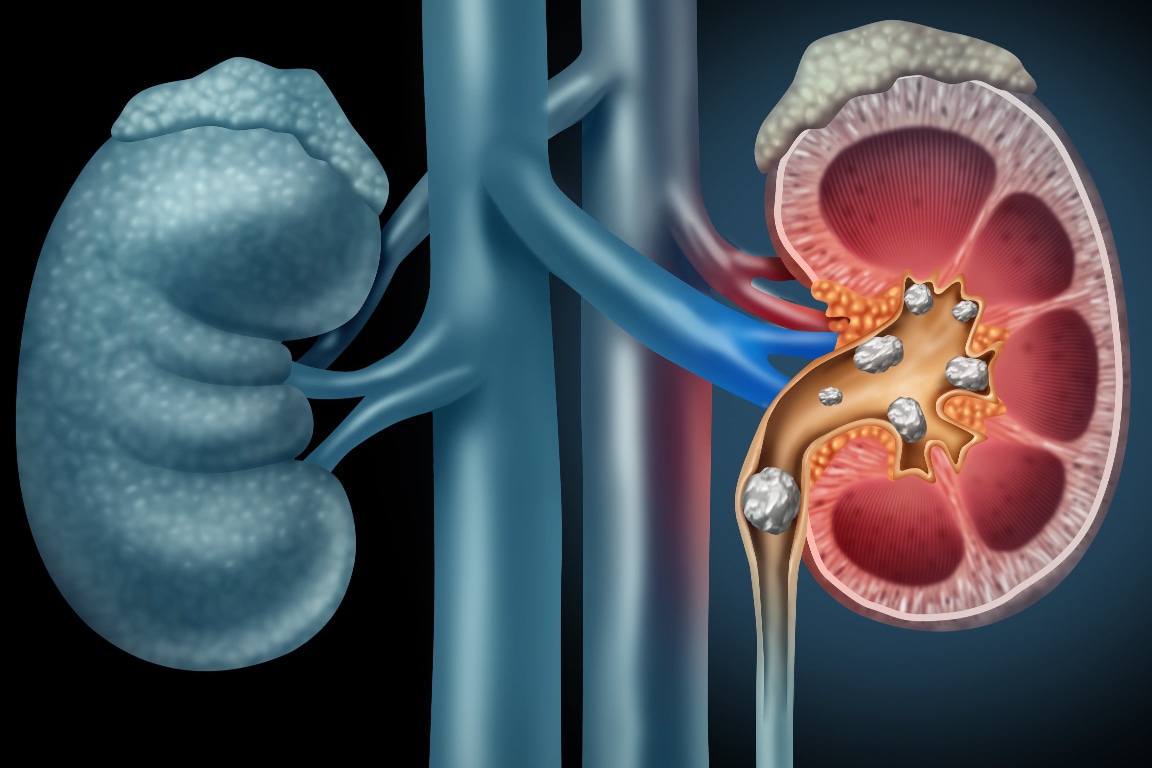

A nefrolitíase é conhecida popularmente como pedra nos rins, mas também pode ser chamada de urolitíase, litíase urinária, litíase renal ou cálculo renal. A sua definição é a presença de cálculo(s) em qualquer parte do sistema urinário.

Tipos de cálculo renal

O tipo de cálculo mais comum é o de cálcio, sendo que representa por volta de 80% dos cálculos. A estrutura é composta principalmente por oxalato de cálcio (75%) e em menor representatividade por fosfato de cálcio (5%).

Os 20% restantes dos cálculos são formados por ácido úrico, estruvita e cisitna. Os cálculos de ácido úrico ou estruvita somam 10% a 15% e os de cistina representam menos de 5%.

A crise de cólica renal ocorre em razão da dilatação do sistema coletor e/ou deslocamento do cálculo pelo ureter.

Na crise de cólica renal a tomografia computadorizada, sem contraste, é o exame de escolha, pois é capaz de determinar a localização, o tamanho e a densidade do cálculo, além de ajudar em diagnósticos diferenciais.